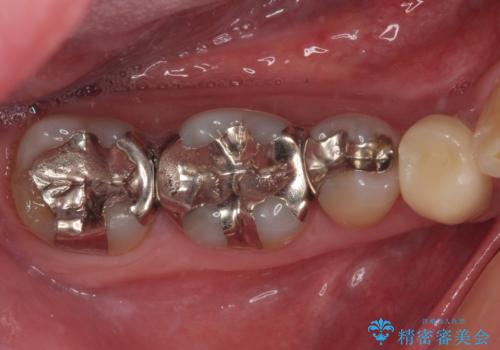

上の銀歯をやり替えたい セラミックインレー修復

- 銀歯をやり替えたいとのことで来院された患者様です。金属の詰め物の大きさ、虫歯の範囲を考慮してセラミックの詰め物(セラミックインレー)で治療を行っていくことにしました。

拡大鏡視野下で、金属の詰め物(メタルインレー)、虫歯の除去を行い、セラミックインレーに適した形に整えました。

歯と歯茎の間に圧排糸と言われる糸を入れてシリコーン印象材にて精密な型どりをしました。

セラミックインレーの装着時には、唾液の侵入を防ぐために、ラバーダム防湿を行いました。